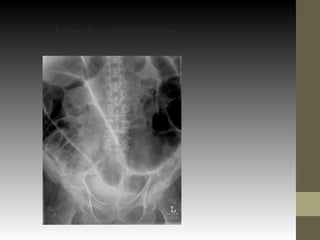

Large bowel obstruction